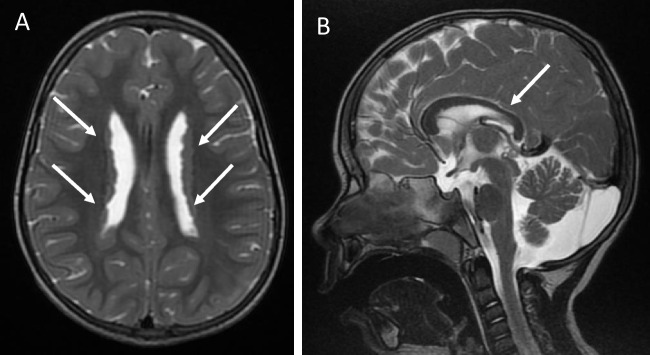

背景:先天性肾病综合征(CNS)是一种罕见的疾病,由足细胞功能和肾小球狭缝隔膜完整性所必需的基因突变引起,包括CRB2(碎屑细胞极性复合物组分2)。CRB2突变与局灶节段性肾小球硬化和囊性肾病伴心室肿大有关,但其完整表型谱尚不清楚。我们描述了纯合子CRB2突变的同卵双胞胎的临床过程,突出了肾移植后的严重并发症。方法:对产前怀疑多囊肾病后诊断为CNS的双胞胎进行随访和全程管理。最初的外显子组测序结果为阴性,但随后的全外显子组测序显示为纯合子CRB2变体。结果:两名双胞胎均出现中枢神经系统,需要加强支持治疗。其他发现包括脑异位、心脏受累和发育迟缓。他们都发展为肾衰竭,需要在儿童早期进行血液透析。移植后,第一个双胞胎死于全身性真菌感染,而第二个双胞胎则出现了与免疫失调相关的并发症,包括移植后淋巴细胞增生性疾病(PTLD)、免疫性血小板减少性紫癜(ITP)、多种病毒血症和新生供体特异性抗体(DSA)。结论:本病例扩大了crb2相关疾病的表型谱,突出了管理方面的挑战,并强调了对罕见病进行基因重新分析的必要性。crb2的相关机制有待进一步研究。

Results: Both twins presented with CNS, requiring intensive supportive care. Additional findings included cerebral heterotopia, cardiac involvement, and developmental delay. They both progressed to kidney failure, necessitating hemodialysis in early childhood. Post-transplant, the first twin succumbed to a systemic fungal infection, while the second developed complications linked to immune dysregulation, including post-transplant lymphoproliferative disease (PTLD), immune thrombocytopenic purpura (ITP), multiple viremias, and de novo donor-specific antibodies (DSA).